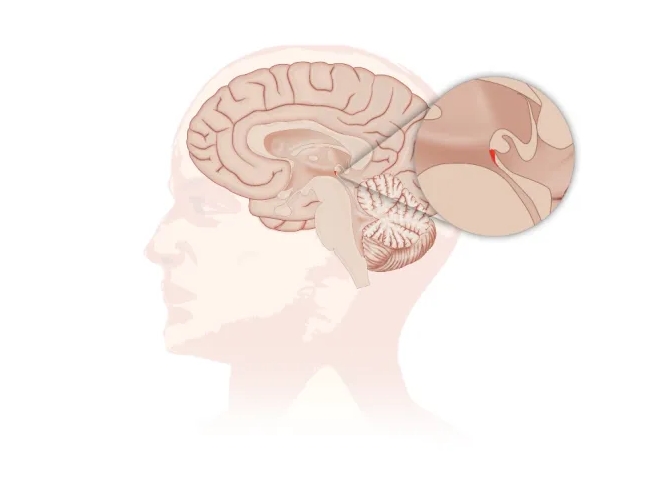

SCO隐藏在大脑中央很深的部位(见图,红色区域)。

上方有大量神经轴突从一侧大脑穿梭到对侧,下方的中脑导水管流淌脑脊液。从分布上看,SCO位于神经连接及脑脊液循环的关键部位(见图)。